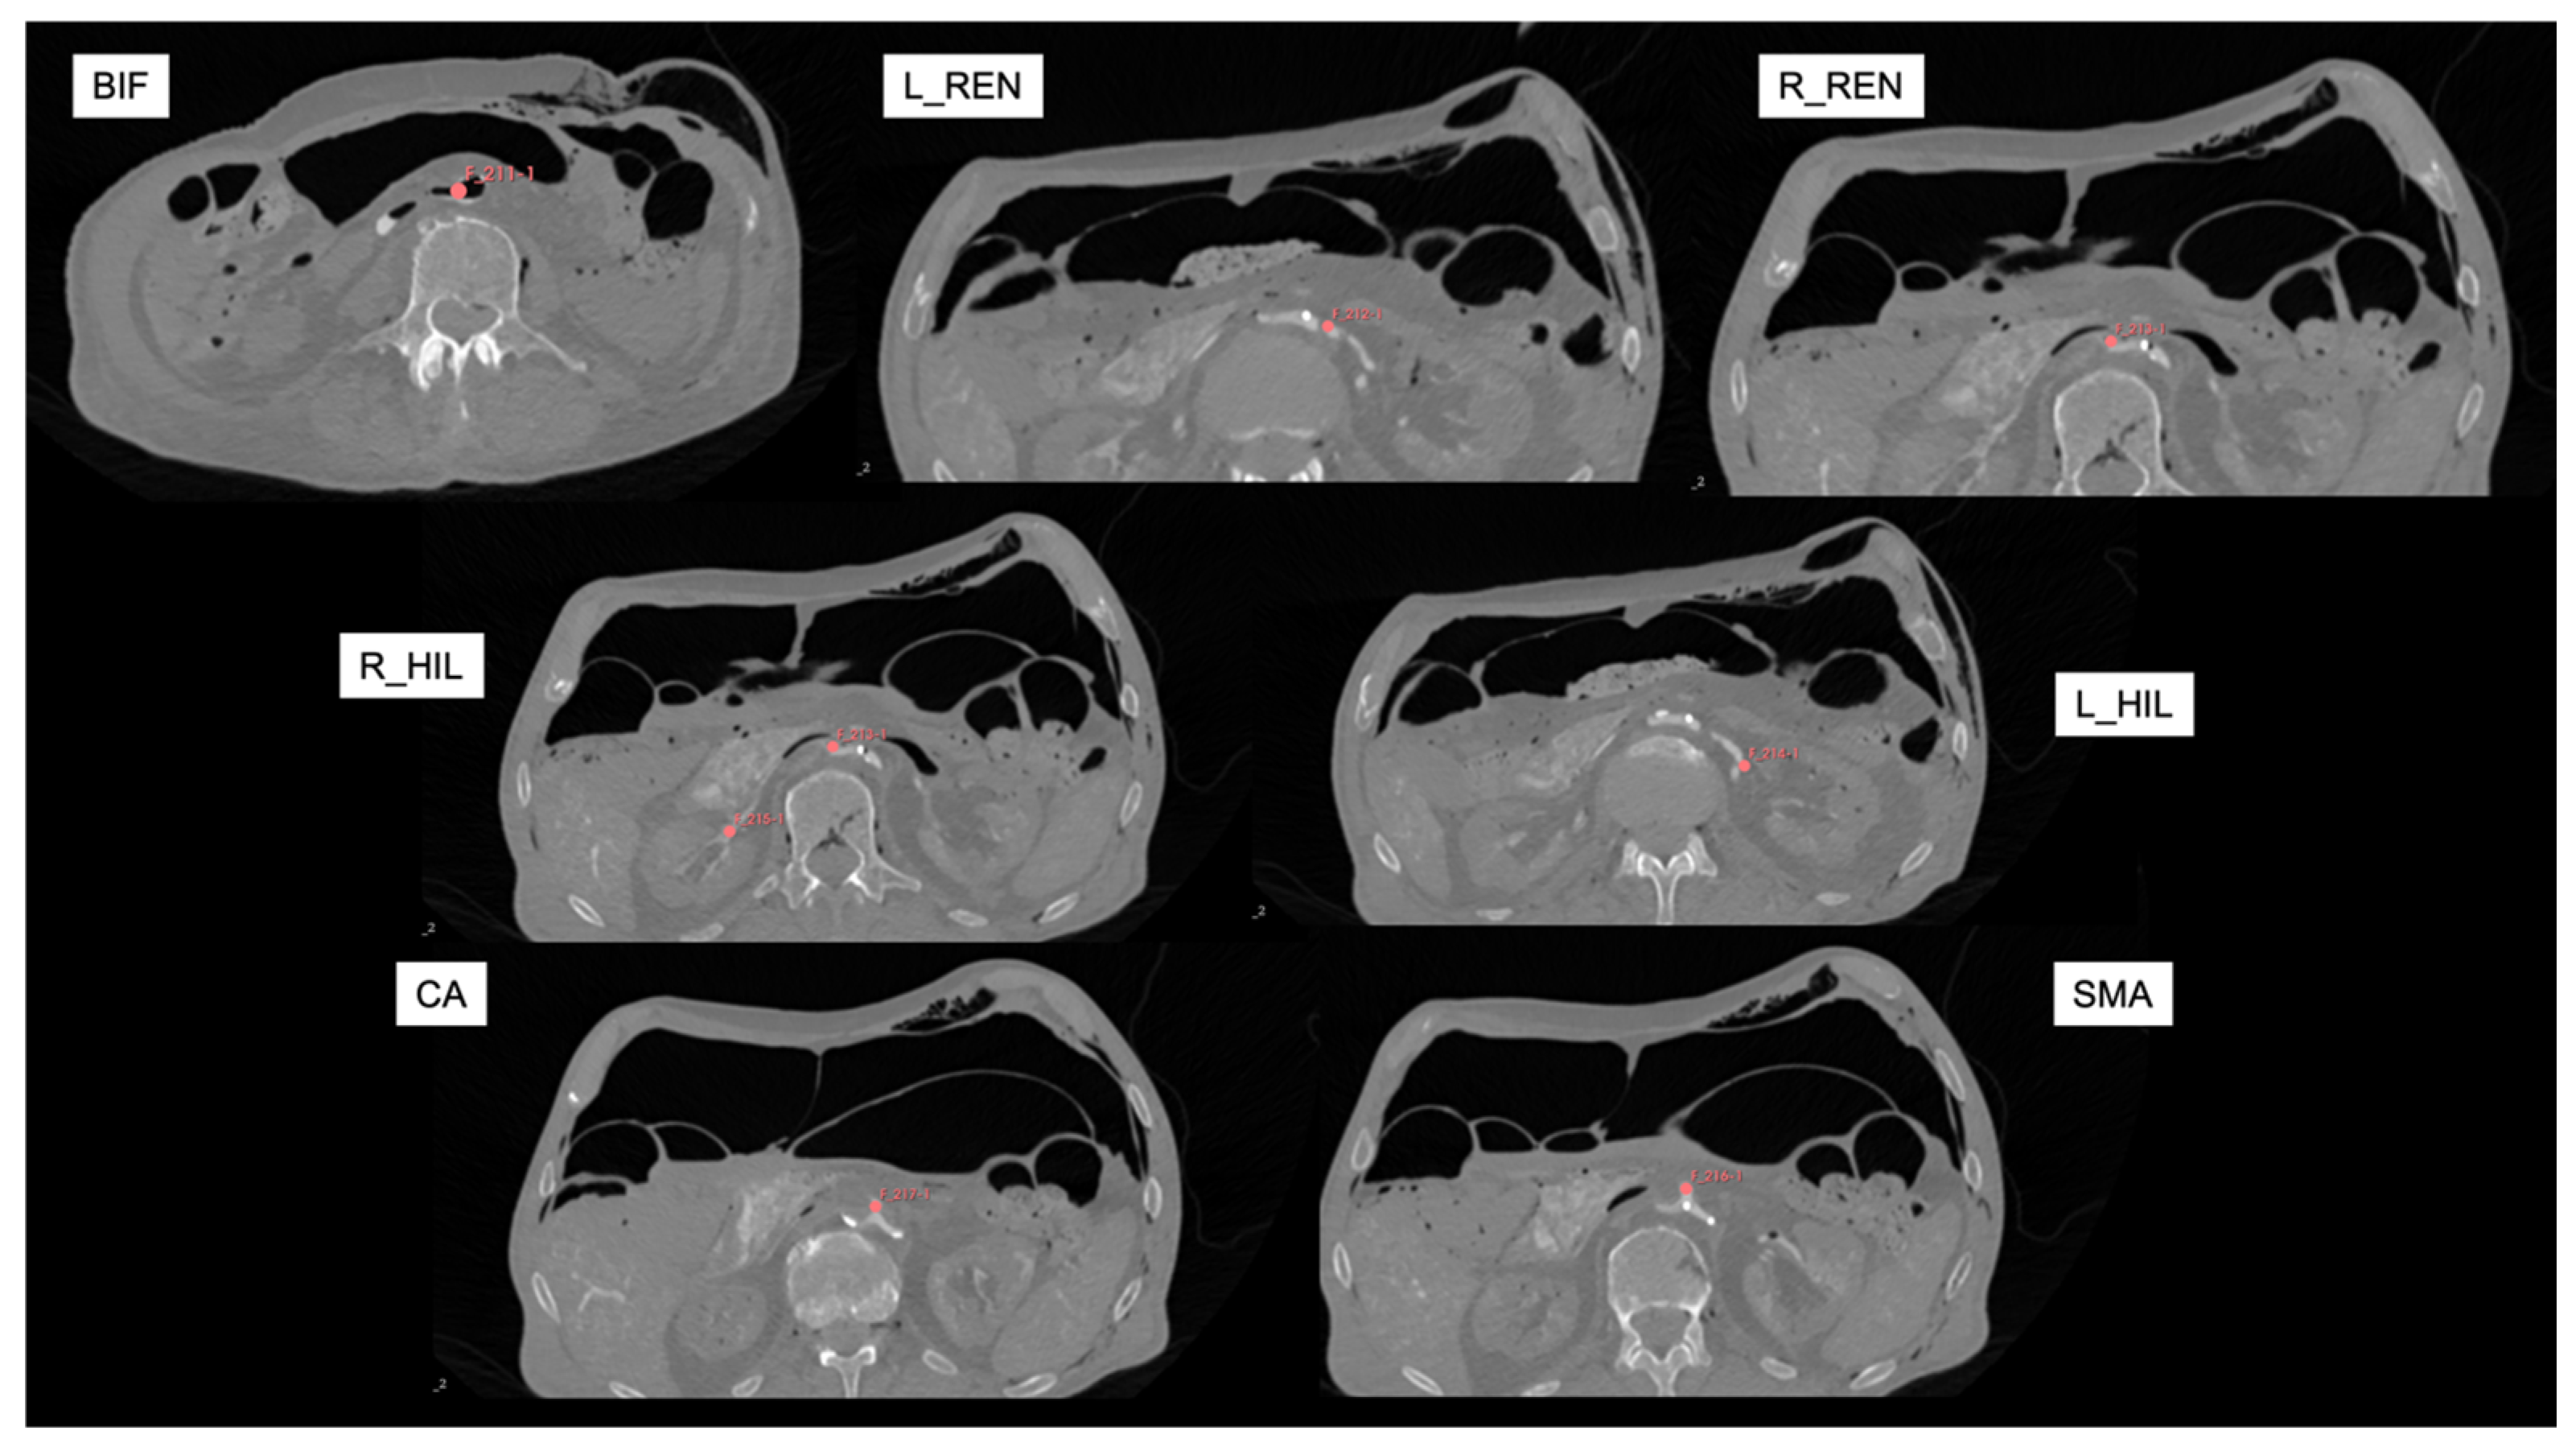

| Anatomical References | Anatomical Target Landmarks | ||

|---|---|---|---|

| R1 | Right Anterior Superior Iliac Spine | P1 | Aortic Bifurcation |

| R2 | Left Anterior Superior Iliac Spine | P2 | Left Renal Artery |

| R3 | Symphysis (upper edge) | P3 | Right Renal Artery |

| R4 | First Sacral Vertebra | P4 | Hilum of the Left Kidney |

| R5 | Tip of the Left XII. Rib | P5 | Hilum of the Right Kidney |

| R6 | Tip of the Right XII. Rib | P6 | Superior Mesenteric Artery |

| R7 * | Distal Tip of the Sternum (excluded) | P7 | Celiac Artery |